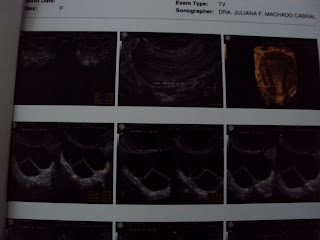

Boa tarde amigas, passei aki rapidinho pra contar que fiz a Inseminação. Acordamos ás 6:00, fui pra clínica fazer a eco, e td ótimo, endométrio cresceu, está em 9,5, romperam 2 folículos em um ovário e 1 no outro. E ela ainda disse que poderiam romper outros , pq ainda ficaram 3. Fui com meu marido em seguida para a Embryo, lá foi feita a capacitação dos esperamátozoides e o preparo. Fomos buscar ás 11:00, o atendimento exelente, a bióloga conversou conosco, disse q estávan muito bom. Lá corremos nós com o precioso isopor na mão, acho q nunca segurei nada com tanto cuidado, nem dinheiro... rsrsrsr Chegando lá um tempo depois fui atendida, meu marido entrou comigo , ñ queria a principio, mas meu médico o convenceu facilmente, rsrsrs, ele acompanhou td, foi ótimo, senti cólica bem finas e depois aumentaram, aiii mas ele disse isso era muito bom, então tá né. O procedimento foi rápido uns 20 minutos, gente foi tudo tão mágico, meu medico foi falando coisas tão boas comigo enquanto fazia, um clima mágico e sereno parecia tomar conta daquela sala, orei muito e tenho certeza que o senhor irá me abençoar. Meu marido segurou minha mão o tempo todo. Fikei de repouso por 30 minutos na clínica, as dores aumentaram bastante, mas como é normal e isso quer dizer que foi injetado corretamente estou aguentando firme, porque ainda está dolorido, inchado, e as cólicas as vezes aumentam. Nada de esforço físico, nos próximos 15 dias , e não vou precisar tomar a progesterona porque meu endometrio está muito bom , 9,5.